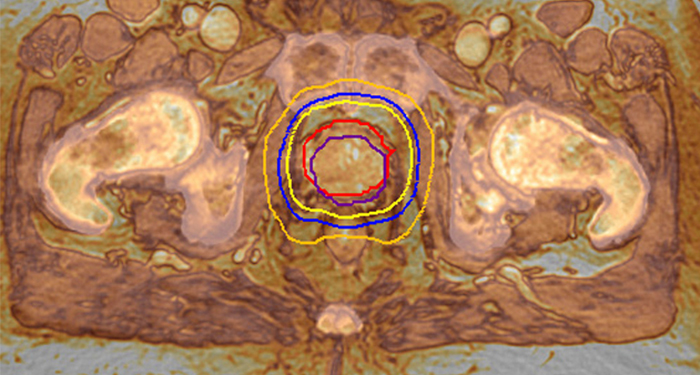

MR-RT XD satisface la necesidad de precisión con avances en calidad de imagen, fidelidad geométrica y posicionamiento reproducible del paciente. Las imágenes de RM de alta calidad se adquieren en la posición de tratamiento, lo que incrementa la precisión en la delineación de los objetivos y estructuras críticas.

Los planes de tratamiento altamente dirigidos se basan en la adquisición de imágenes de RM realizadas en la posición de tratamiento. Con MR-RT XD puede adquirir imágenes de RM de alta calidad en la posición de tratamiento, lo que aumenta la precisión en la delineación de objetivos y las estructuras críticas.